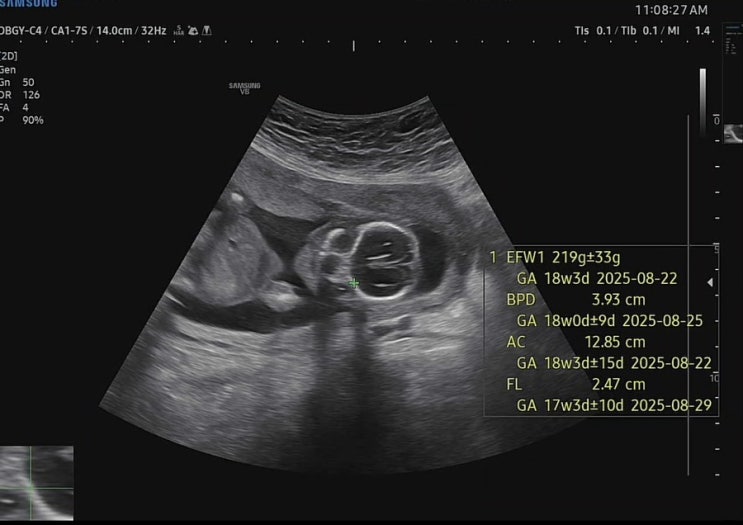

임신 중기 20주 5일 정기검진

안녕하세요 별이맘스리입니다 4주만에 가는 병원이었는데 검사할 것 없어서 그런지, 아니면 이제 느껴지는 ...